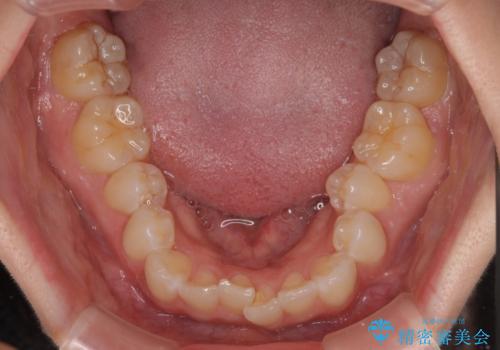

- 上下前歯のデコボコとディープバイトを気にして来院された患者様です。

歯列全体に叢生があり、舌の突出癖が認められたため、突出癖が改善されない場合には口元が突出するリスクが考えられました。

なかなか舌の突出癖が改善できず、上下前歯が非接触となる期間が長く続きました。

アンカースクリューの活用と、舌のトレーニングを何度も指導し、出っ歯になることなく無事に治療を終えることができました。